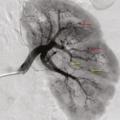

Les atteintes digestives et rénales sont vasculaires, en lien avec des sténoses des moyens vaisseaux, responsables de phénomènes ischémiques et/ou de microanévrismes (fig. 4).6 Leur diagnostic se confirme à l’imagerie, notamment par une angiotomodensitométrie (TDM). L’artériographie, examen de référence, peut s’avérer nécessaire, à visée diagnostique en cas de négativité de la TDM,2 mais surtout à visée thérapeutique, permettant une artério-embolisation en cas d’hémorragie grave.

L’atteinte rénale se manifeste soit par une hypertension artérielle isolée, parfois sévère, soit par une authentique néphropathie vasculaire (insuffisance rénale aiguë, protéinurie tubulaire +/- hématurie microscopique, stigmates biologiques de microangiopathie thrombotique).16 Elle est en lien avec des sténoses, pouvant aussi entraîner des infarctus rénaux. Les microanévrismes des artères rénales et de leurs branches peuvent être responsables d’hématomes sous-capsulaires ou rétropéritonéaux.17 Si l’insuffisance rénale ne se voit que dans 12 % des PAN,5,6 cette néphropathie vasculaire, non glomérulaire, représente un enjeu diagnostique majeur. Contrairement aux autres vascularites, notamment celles ­associées aux anticorps anticytoplasme des polynucléaires neutrophiles (antineutrophil cyto­plasmic antibodies [ANCA]), la biopsie rénale ne doit pas être réalisée avant d’avoir exclu les microanévrismes en artériographie, au ris­que de complications hémorragiques.16,18

L’imagerie artérielle peut suffire à poser le diagnostic, en cas de suspicion clinique et de présence d’anévrismes sacciformes ou fusiformes, de sténoses des artères de moyen calibre, notamment rénales, hépatiques ou digestives.2,4 En première intention, une imagerie non invasive telle que l’angio-TDM ou l’angio-­IRM (en cas de contre-indication aux produits de contraste iodés) est recommandée mais nécessite un regard exercé de la part du radiologue. L’artériographie reste l’examen de référence en cas de doute diagnostique, mais n’est réalisée qu’en deuxième intention, compte tenu d’éventuelles complications, à type d’hématome, de faux anévrismes au point de ponction ou de néphropathie aux produits de contraste.2 Elle peut aussi jouer un rôle thérapeutique, en cas de saignement sévère, permettant de réaliser une embolisation.